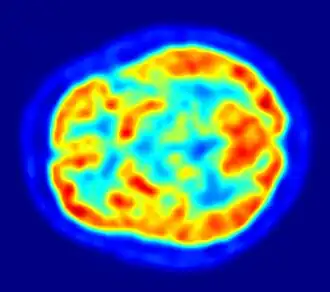

Сцинтиграфия миокарда

Сцинтиграфия миокарда является ведущим методом диагностики ИБС во всем мире, ежегодное количество пациентов в Европе и США превышает 10 миллионов человек. При проведении исследования пациенту вводится радиофармпрепарат, тропный к неизмененным кардиомиоцитам сердечной мышцы (миокарда), с целью их визуализации. Сцинтиграфия миокарда проводится в 2 этапа: исследование с нагрузкой и в покое. Метод обладает широкими возможностями в диагностике ИБС. Производится выявление преходящей ишемии миокарда, обусловленной поражением коронарных артерий атеросклеротическими бляшками, в том числе у больных без клиники стенокардии. В зависимости от локализации и распространенности преходящей ишемии определяются показания к коронарной ангиографии. У пациентов с перенесенным острым инфарктом миокарда проводится определение его локализации и объёма поврежденного миокарда вне зависимости от сроков давности. Сцинтиграфия миокарда является высокоточным методом оценки эффективности медикаментозного лечения, эффективности эндоваскулярных вмешательств (коронарной баллонной ангиопластики со стентированием), операций на открытом сердце (коронарного шунтирования), кардио-реабилитации, включая усиленную наружную контрапульсацию и ударно-волную терапию. Приблизительное время проведения исследования составляет 2—3 часа.

Сцинтиграфия головного мозга

Однофотонная эмиссионная компьютерная томография головного мозга проводится с радиофармпрепаратами (РФП), накапливающимися пропорционально мозговому кровотоку. Исследование проводится через 20—30 минут после введения РФП. В результате производится топическая диагностика перенесенного инсульта, ишемии головного мозга, обусловленной поражением церебральных артерий, нарушений перфузии при нейродегенеративных заболеваниях. Метод позволяет оценивать эффект от лекарственной терапии, эндоваскулярных вмешательств на сонных, вертебральных и мозговых артериях, эффективность реабилитационных мероприятий. Время проведения исследования составляет менее 1 часа.